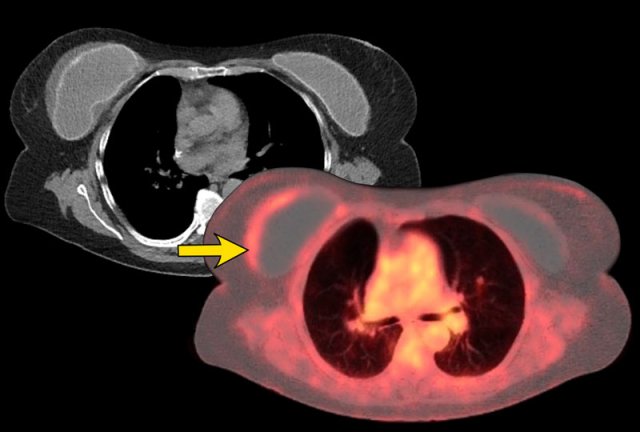

Silicone granulomas

Silicone granulomas remainig after removal of breast implant because of previous extracapsular rupture in 2013.

Silicone granulomas can manifest as masses with suspicious morphology and enhancement dynamics on breast MRI or with increased FDG uptake on PET CT.

They

can present at the periphery of the prosthesis or in breast tissue after

rupture.

The presence of silicone implants and awareness of the possibility of a rupture and formation of silicone granulomas may help in facilitating a correct diagnosis (ref).